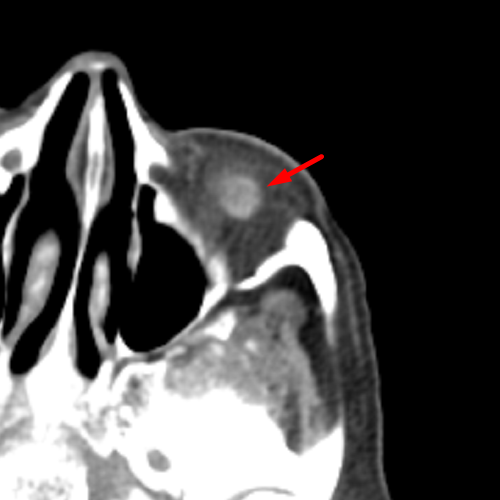

Age: 79

Sex: Female

Indication: Adenoid Cystic Carcinoma